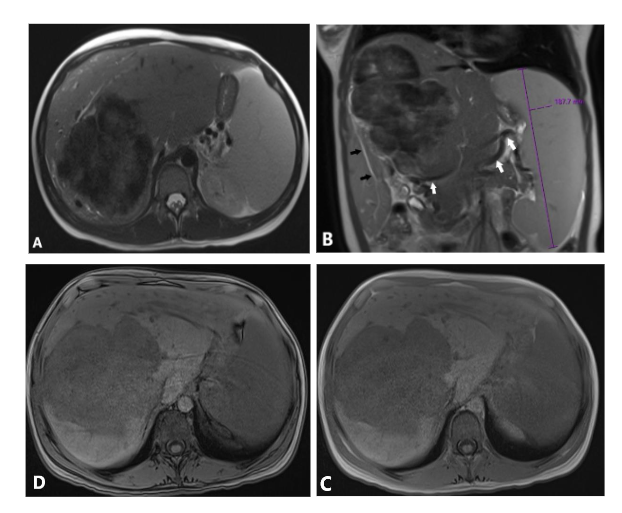

A 17-year-old female, previously healthy, presented with abdominal pain and pruritus for several months. She noticed jaundice in her eyes for the last two weeks but denied acholic stools. These symptoms were associated with a 10-pound weight loss and fatigue. She was not on any steroids or oral contraceptive pills. Initial lab data showed a total bilirubin of 4.7 mg/dL (0.0-1.2), alkaline phosphatase of 390 unit/L (40-130), AST of 101 unit/L (10-45), and ALT of 162 unit/L (7-45). Abdominal ultrasound (Figure 1) showed a large lobulated mixed echogenicity mass centered on the right hepatic lobe containing several hypoechoic components with posterior acoustic shadowing without a discernible central scar. Color Doppler showed scanty peripheral vascularity without significant internal vascularity. The spleen was moderate to markedly enlarged with a craniocaudal dimension of approximately 19 cm. Upon further laboratory evaluation, CA 19-9 was 68.8 units/mL (Nl: up to 35) with normal serum alpha-fetoprotein and beta-HCG. Abdominal MRI (Figure 2) showed a large, predominantly T1/T2 hypointense mass with delayed progressive enhancement (Figure 3). There was no signal drop throughout the lesion on out-of-phase images to suggest a fat component. DWI and ADC mapping demonstrated a predominantly hypointense signal (T2 blackout). No central scar was appreciated within the hepatic lesion. Mild, regular dilation of peripheral intrahepatic biliary ducts was also identified due to the mass effect on the biliary system. Splenomegaly and collateral vessels were present. There was no tumoral invasion or thrombosis of the inferior vena cava.

Figure 2. (A, B) Axial and coronal views of T2 weighted images (WI) show predominantly hypointense large hepatic mass. Note intrahepatic mild biliary dilation distal to the large mass (black arrows), splenomegaly, and multiple signal void collateral vessels (white arrows). In-phase (C) and out-phase (D) images do not show signal drop on out-phase image to suggest fat component. Diffusion weighted image (E) and Apparent Diffusion Coefficient (F) show predominantly T2 black out pattern (white arrowheads) and mild T2 shine-through centrally.

The tumor exhibits low signal intensity on both T2-weighted and diffusion-weighted imaging (DWI), a

characteristic attributed to its high collagen content. The dense fibrous tissue shortens the T2 relaxation time, resulting in a markedly dark appearance—a phenomenon commonly observed in tumors with extensive fibrous components¹¹. The “T2 blackout” phenomenon has also been observed in hematomas, attributed to the paramagnetic properties of deoxyhemoglobin in the blood¹².

Delayed Contrast Enhancement: Delayed contrast enhancement, a hallmark imaging feature of fibrous tumors¹³,¹⁴, is also evident in this case.